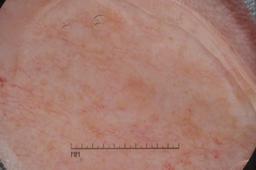

ISIC-DICM-17K (ISIC Dermoscopic Images and Clinical Metadata 17K) is a curated and balanced dataset derived from the International Skin Imaging Collaboration (ISIC) Archive Gallery. It comprises 17,060 dermoscopic images and clinical metadata (8,530 melanoma and 8,530 non-melanoma classes).

For more details, please follow the project’s GitHub repository: https://github.com/mmu-dermatology-research/isic-dicm-17k

This dataset was used in this study and benchmark to explore the effectiveness of multimodal learning for skin lesion classification:

S. Ahammed, X. Cui, W. Lu and M. H. Yap, "Skin Lesion Classification using Dermoscopic Images and Clinical Metadata: Insights from Multimodal Models," 2025 IEEE/CVF Conference on Computer Vision and Pattern Recognition Workshops (CVPRW), Nashville, TN, USA, 2025, pp. 222-230, DOI: 10.1109/CVPRW67362.2025.00027